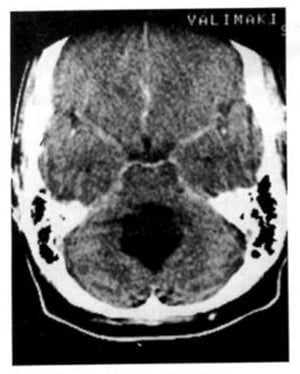

2.2. Xuất huyết (Hình 1.68)

Dấu hiệu XQCTĐT:

– Tổn thương mật độ cao gây chèn ép hoặc tắc nghẽn não thất 4 dẫn tới não úng thủy.

Chú giải:

– Xuất huyết vào trong bể có thể xuất hiện như những lớp mật độ cao nằm kế cận lều tiểu não hoặc các bể.

Hình 1.68. Xuất huyết trong não thất. Não thất 4 chứa máu, giãn nở và có mật độ cao (mũi tên). Các sừng thái dương giãn nở chứng tỏ có tắc nghẽn.